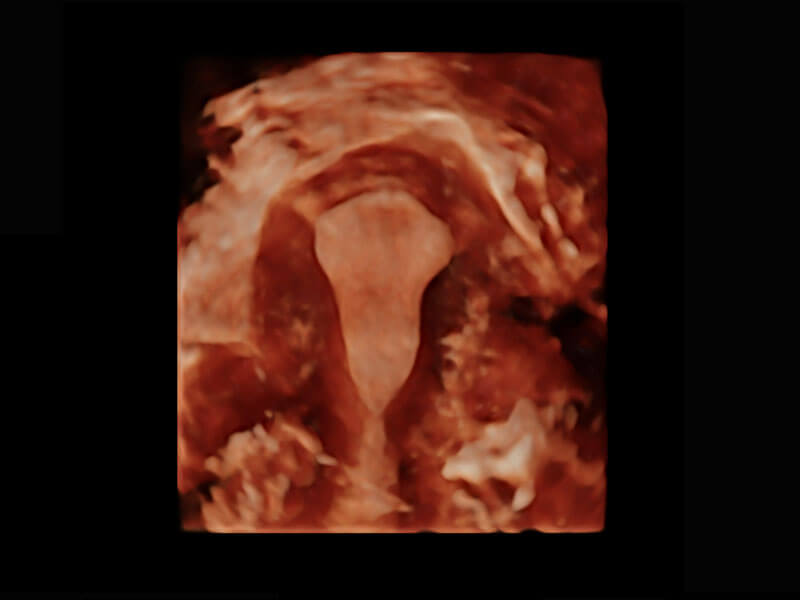

腔内三维-光影成像

P60搭载一系列胎儿心脏成像技术,实现精细的胎儿心脏评估。

胎心容积成像